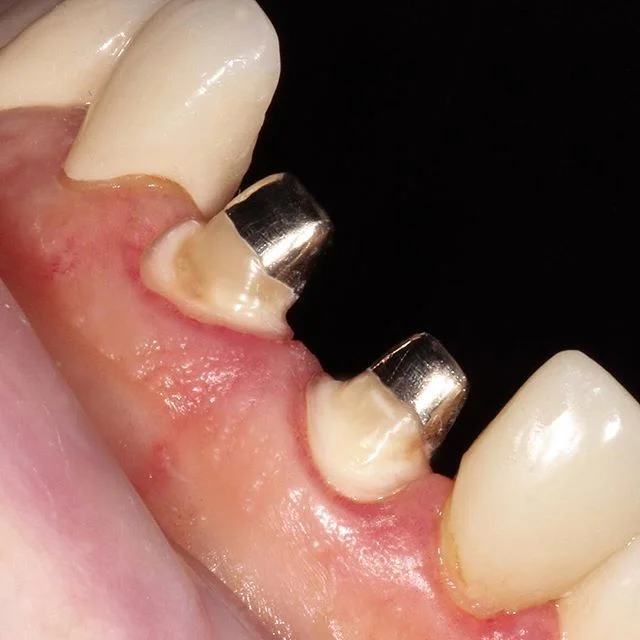

*Example of acceptable metal collar